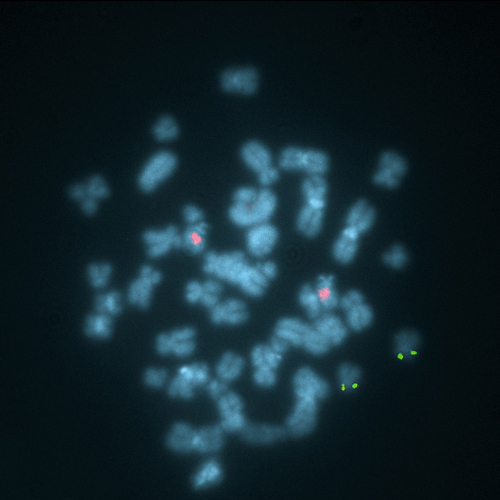

KBI-10503

1q21 / 8p21